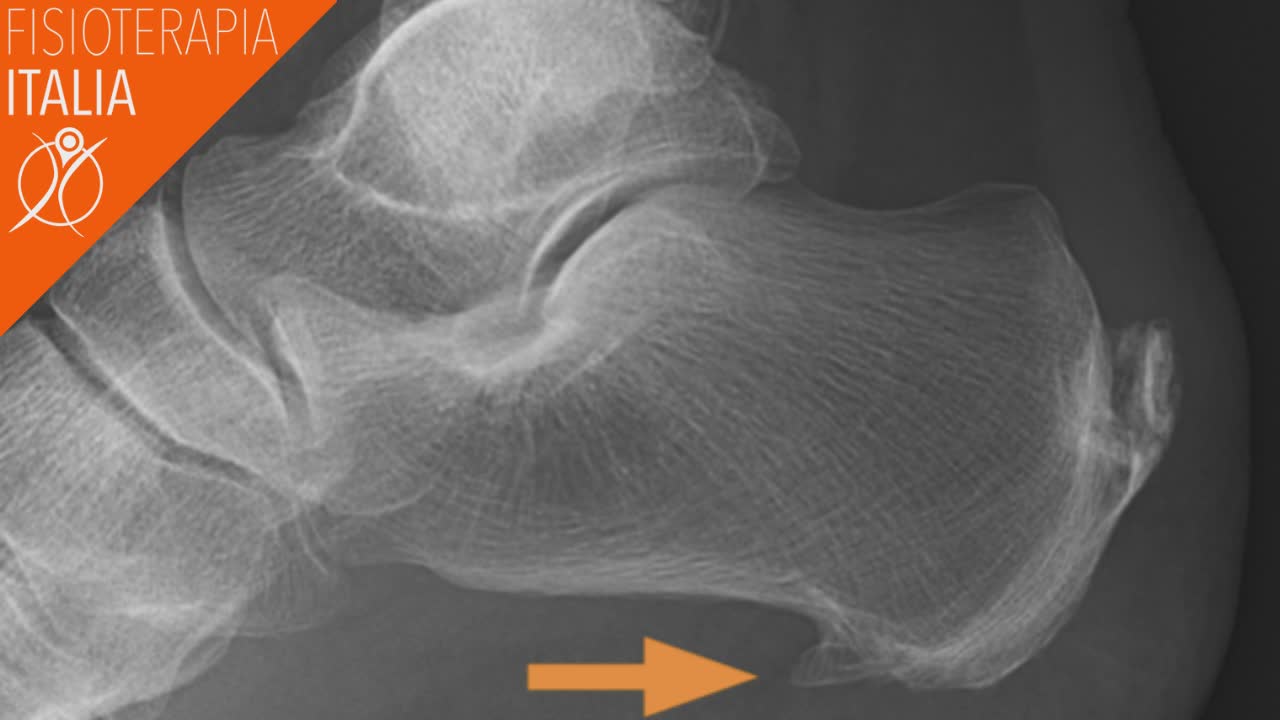

Lo sperone calcaneare è una piccola sporgenza ossea di circa 1 cm o poco più che si trova sulla faccia anteriore-inferiore del tallone, ed assomiglia ad una piccola spina o becco che parte dal calcagno in direzione della pianta del piede (nelle foto sotto è ben visibile la sua presenza ed il suo posizionamento).

L'area interessata può essere percepita calda e dolente al tatto, con sintomi che possono anche diffondersi su tutto l'arco del piede: solo in rari casi è possibile percepire al tatto una piccola sporgenza ossea. Alcuni speroni calcaneari, o spine calcaneari, potrebbero non provocare alcun tipo di fastidio ed alcun tipo di cambiamento nei tessuti molli o nelle ossa che circondano il tallone: per questo motivo, la loro presenza è rilevabile e visibile solo attraverso un approfondimento diagnostico, come i raggi X e le ecografie o risonanza magnetica.

Un esame radiografico però non sempre evidenzia l'esistenza di una spina calcaneare. Un' ulteriore esame diagnostico come l’ecografia dei tessuti molli chiarisce la presenza o meno di fascite plantare, una patologia che può simulare la presenza di sperone calcaneare.